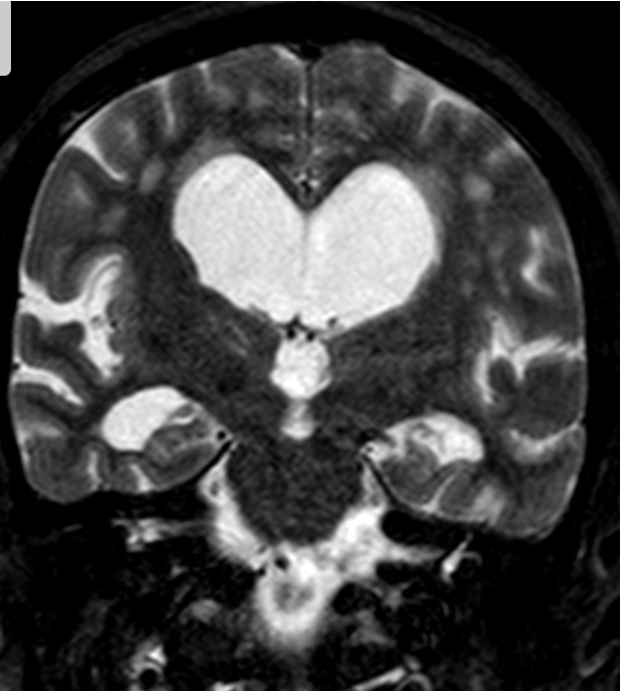

Marked obstructive hydrocephalus due to fourth ventricular outlet obstruction by fine septations

dandy walker malformation

This case illustrates a classic Dandy Walker malformation with associated aqueduct stenosis and obstructive hydrocephalus, a common associated feature

(although not part of the Dandy walker triad: